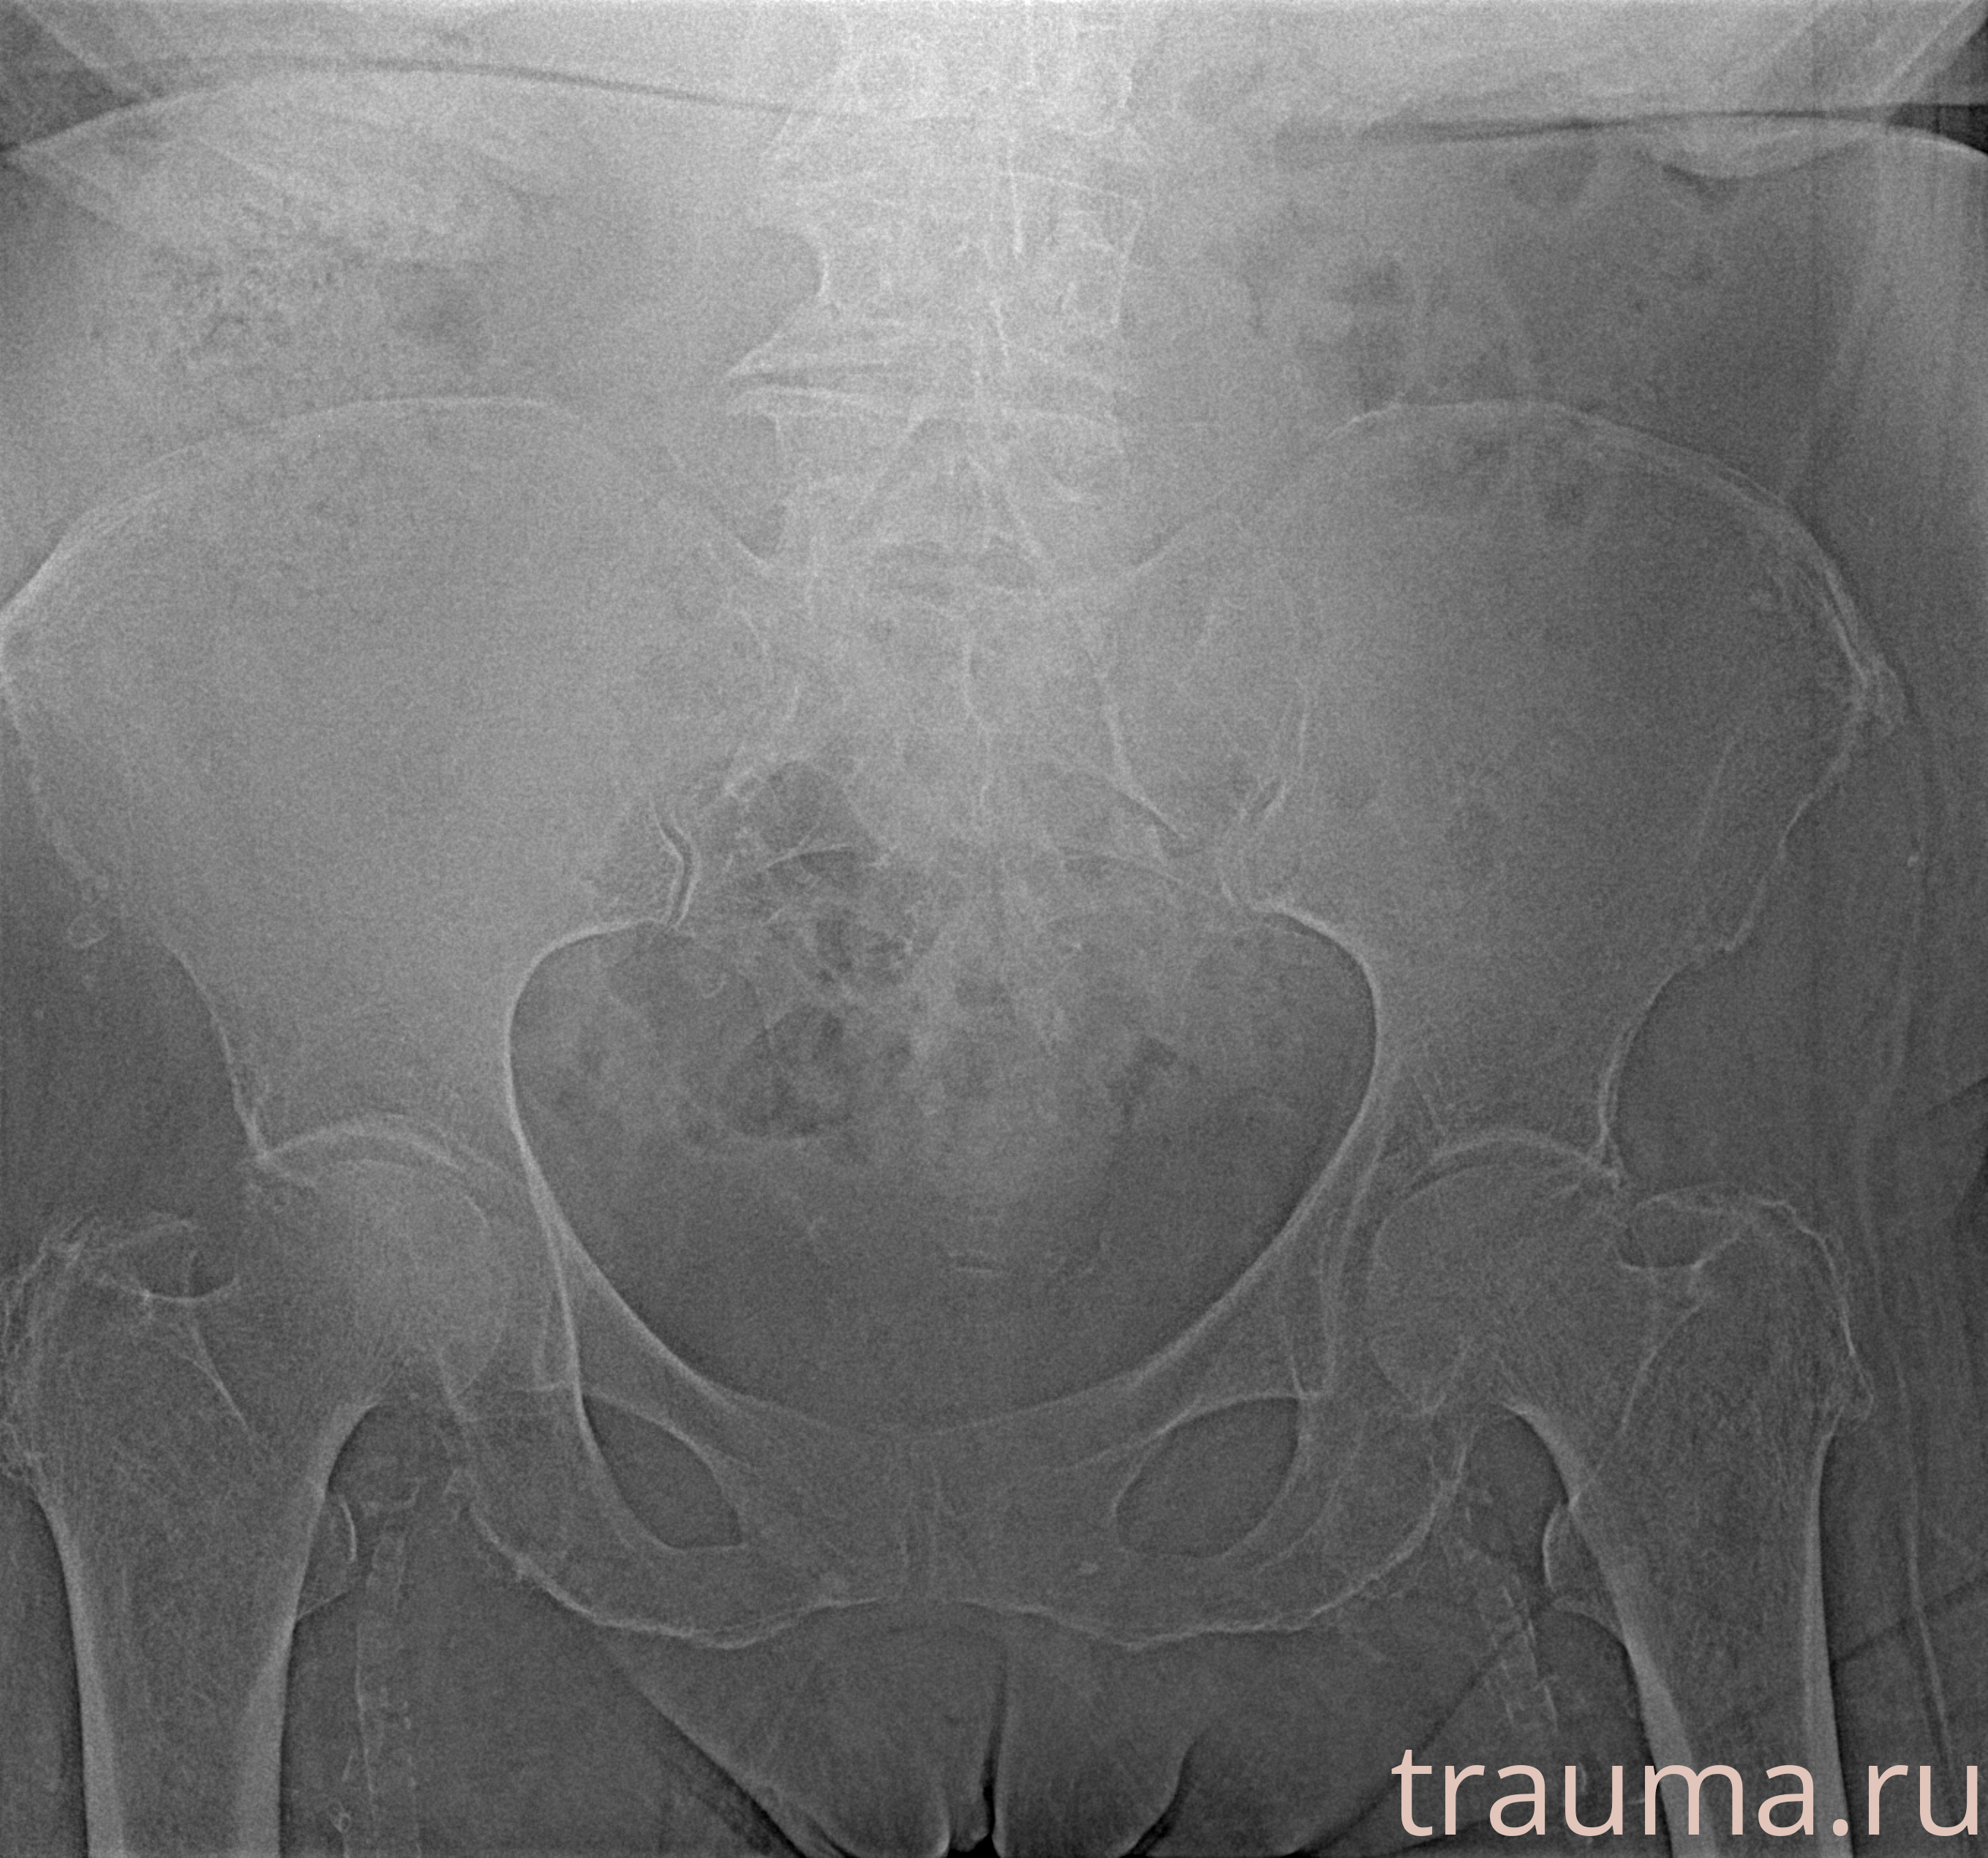

Рентгенограммы

Рентген на дому: по вашему адресу приезжает врач-рентгенолог, травматолог-ортопед с мобильным рентгеновским аппаратом, проводит диагностику травмы или заболевания, делает необходимые рентгенограммы, дает рекомендации по дальнейшему лечению. Получить качественные снимки в домашних условиях возможно благодаря уникальной методике, разработанной МосРентген Центром для института  Склифосовского